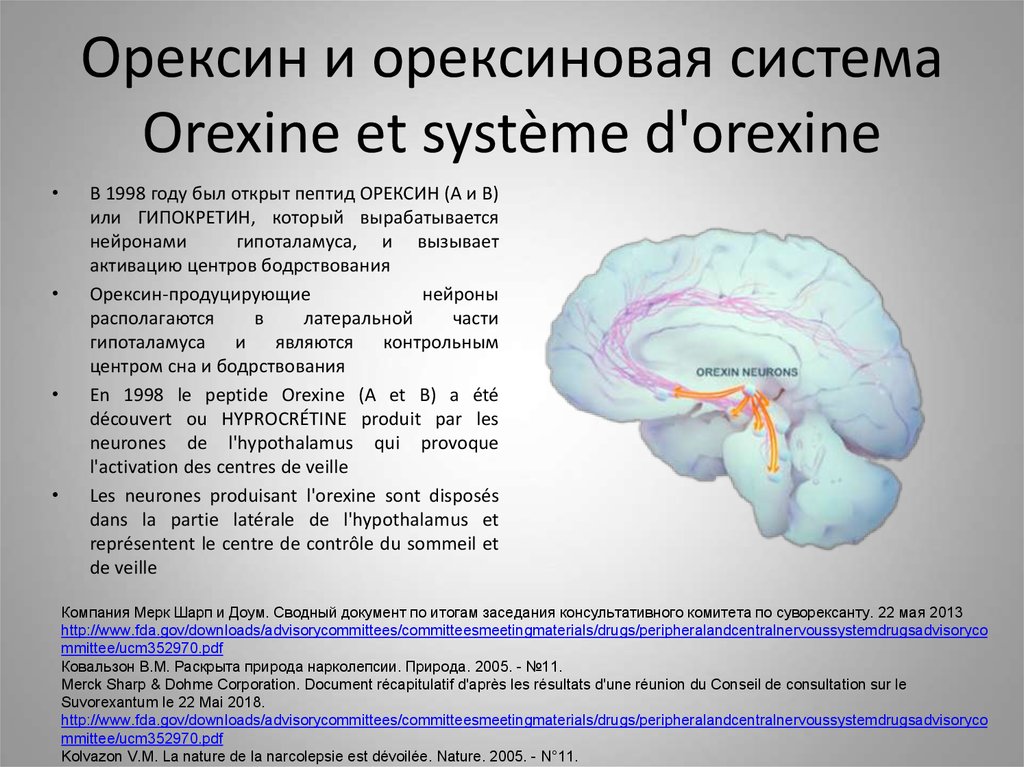

Как работает центр насыщения в гипоталамусе: визуальные иллюстрации